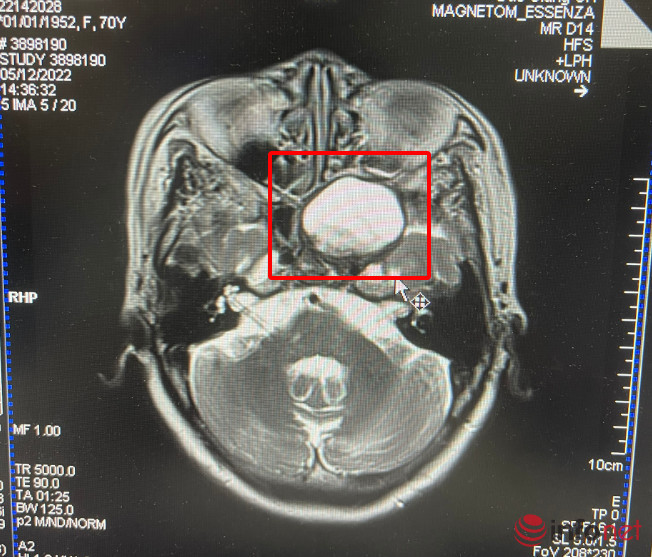

Bệnh nhân nhập viện trong tình trạng co giật, nôn liên tục, đau nhiều vùng trán. Bệnh nhân được chỉ định chụp CT, phim chụp cho thấy hình ảnh vùng xoang bướm có xuất hiện u nhầy quá to, choán chỗ và xâm lấn ăn mòn một phần thành xoang, đè đẩy thùy thái dương.

Bệnh nhân được chỉ định kiểm tra thị lực: 2 mắt đếm ngón tay 50cm. Khối u có kích thước lớn 32x32x38 mm, lấp đầy thành xoang bướm xâm lấn nội so chèn ép hố yên.

Bác sĩ Hoàn cho biết thêm, nguyên nhân gây u nhầy xoang bướm hiện chưa được xác định. Ở trường hợp bệnh nhân này: tiền sử viêm xoang bướm nhưng bệnh nhân chủ quan không kiểm tra nên để khối u phát triển quá to kích thước 3,2x3,2x3,8cm, bên trong lòng xoang lại có tổ chức nấm và mủ nên triệu chứng đau đầu, nôn rầm rộ của bệnh nhân là khá điển hình.